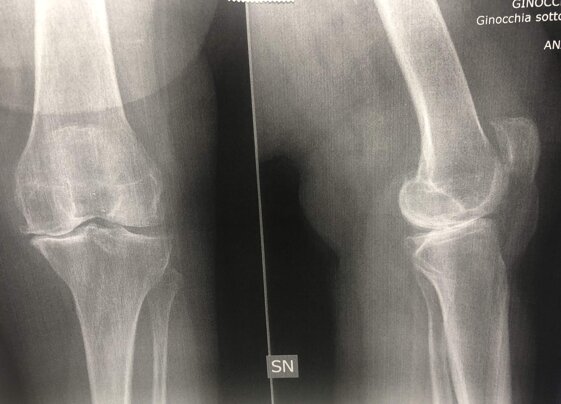

A sinistra radiografie pre-operatorie il AP e LL che evidenziano una grave gonartrosi diffusa con presenza di osteofiti periarticolari e deformità associata (ginocchio varo).

A destra radiografia post-operatoria in AP di intervento chirurgico di artroprotesi di ginocchio cementata, unico trattamento possibile con pz che presentava dolore continuo e zoppia. Ho utilizzato una protesi con risparmio del legamento crociato posteriore (CR) chiamata Persona proprio perché altamente anatomica, cioè molto rispettosa dell’anatomia del ginocchio del singolo paziente

A destra radiografia post-operatoria in AP e LL di intervento chirurgico di artroprotesi di ginocchio cementata, unico trattamento possibile con pz che presentava dolore continuo e zoppia. Ho utilizzato una protesi con risparmio del legamento crociato posteriore (CR) chiamata Persona proprio perché altamente anatomica, cioè molto rispettosa dell’anatomia del ginocchio del singolo paziente. La paziente presentava un sovrappeso per cui ho optato per una componente protesica tibiale con un fittone più lungo proprio per avere più resistenza